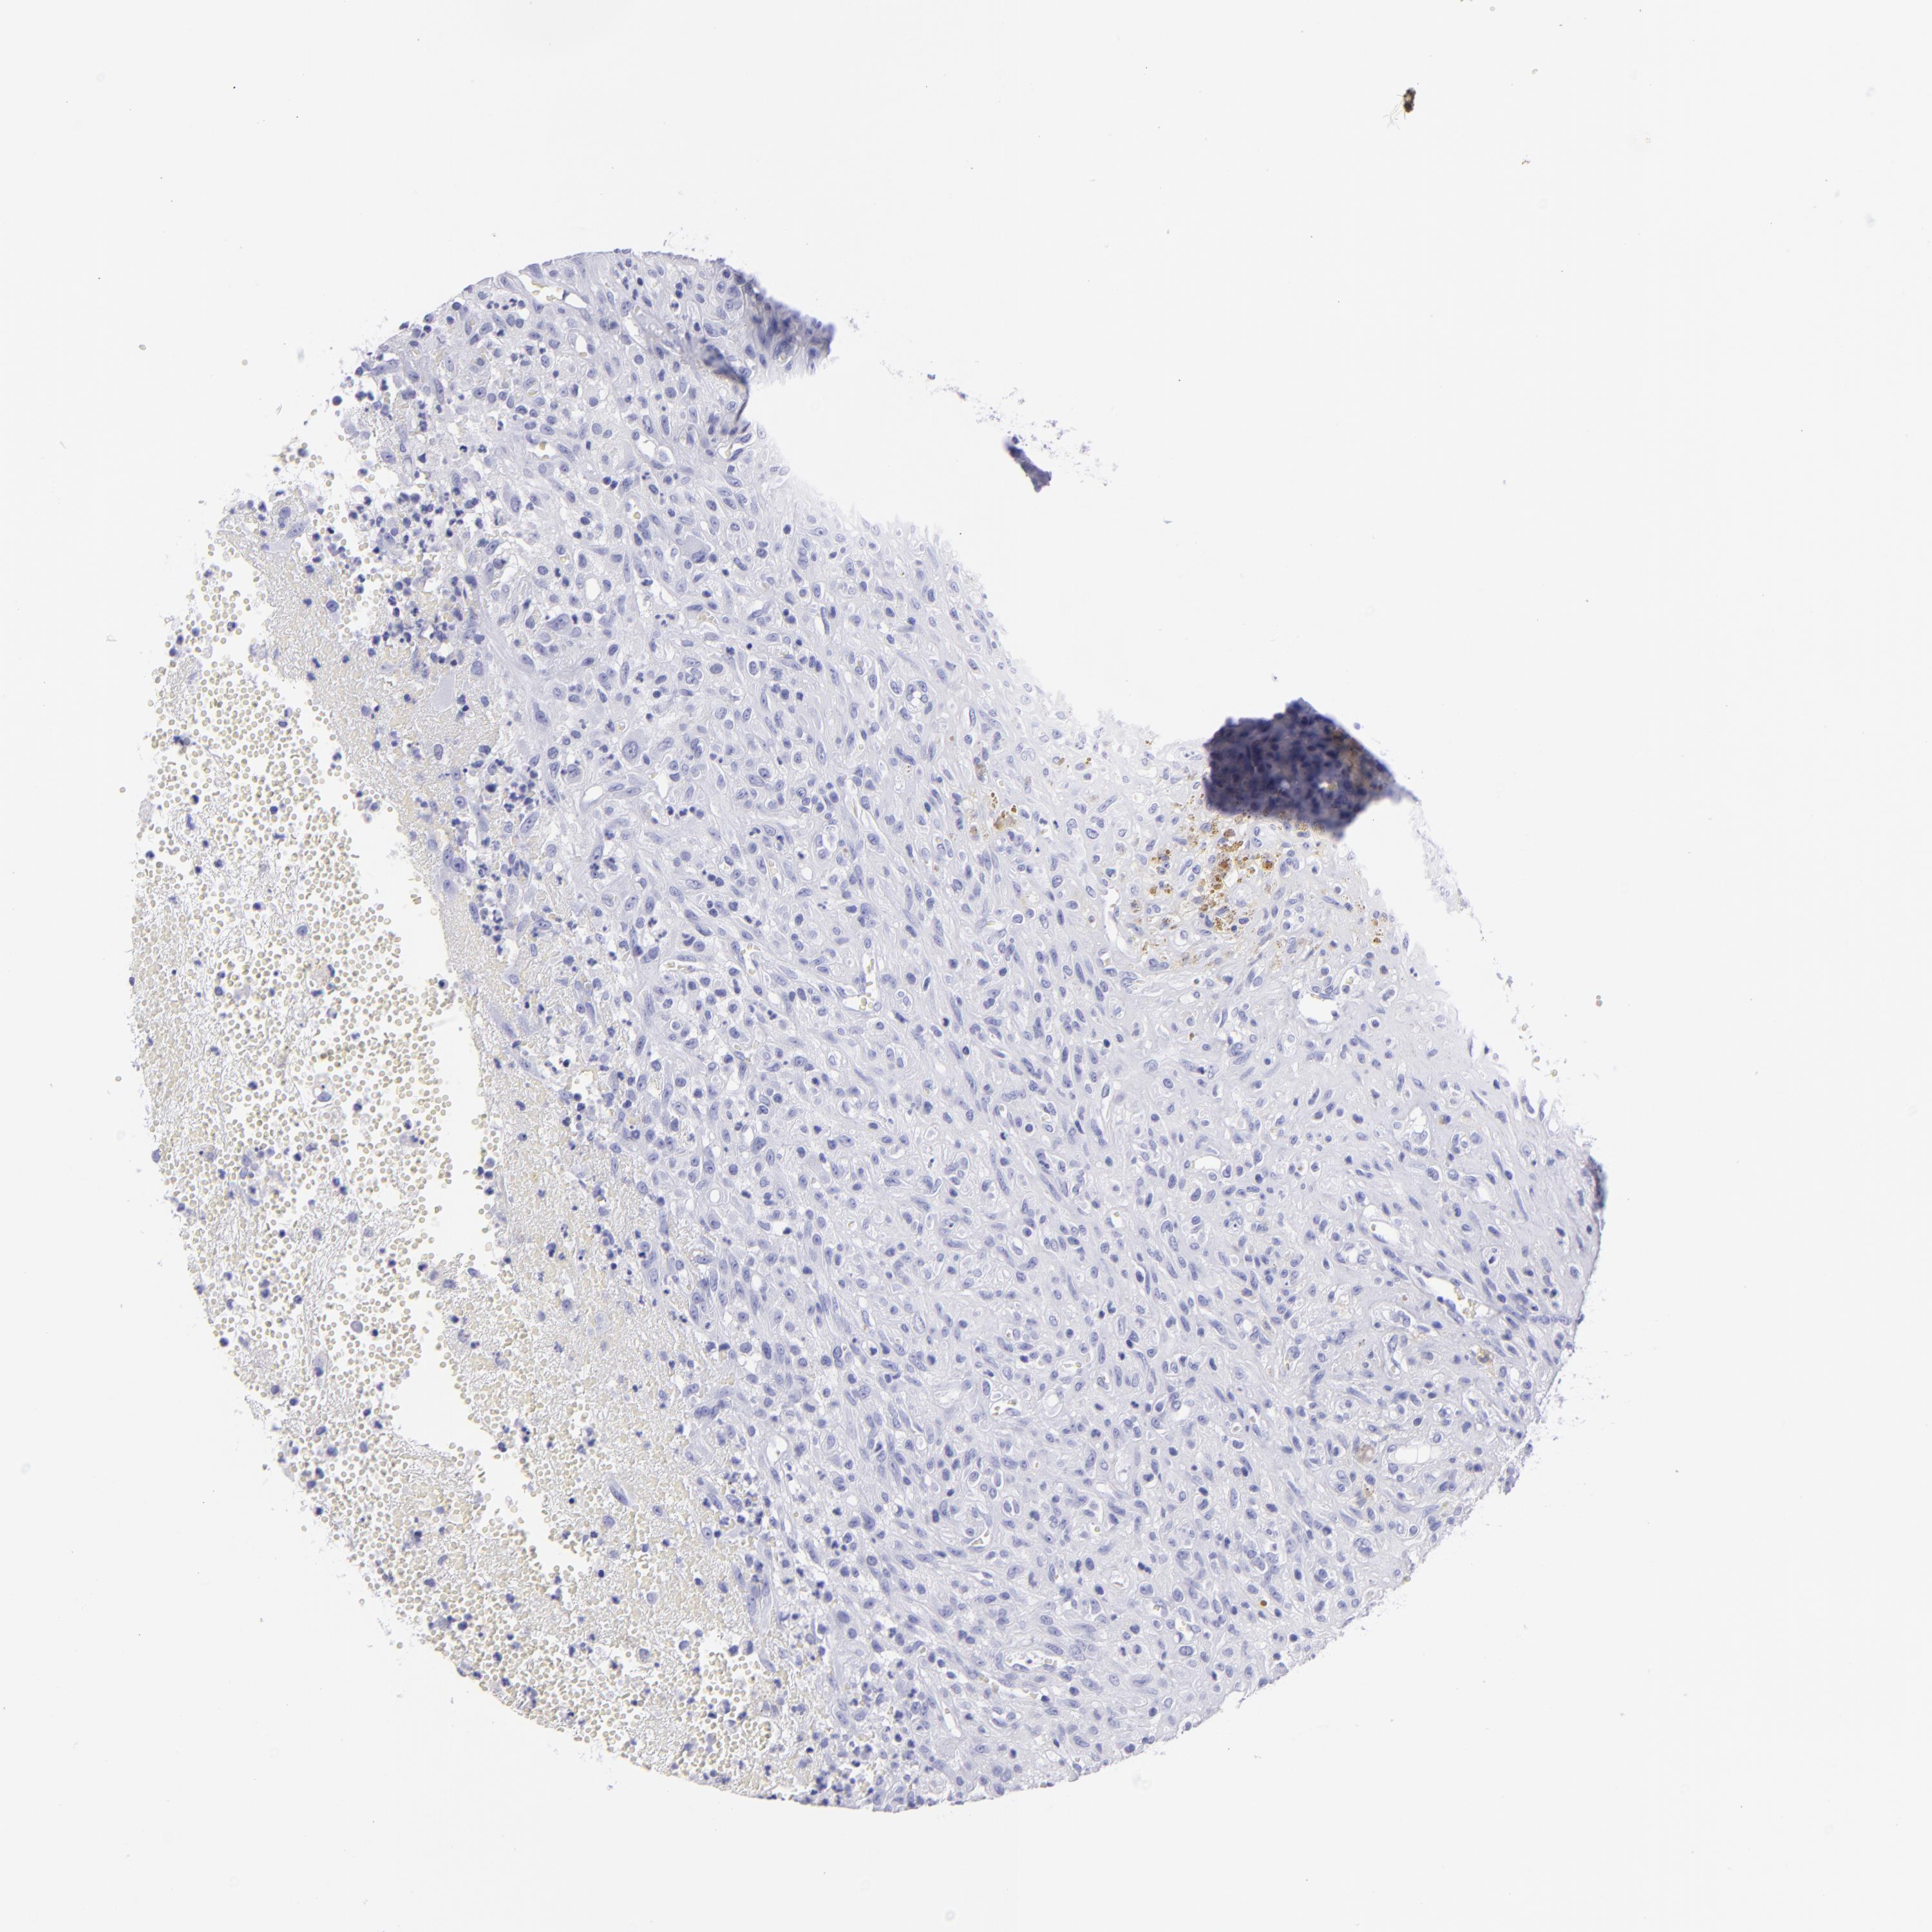

GLIOMA - Protein expressioni

A mouse-over function shows sample information and annotation data. Click on an image to view it in a full screen mode. Samples can be filtered based on level of antibody staining by selecting one or several of the following categories: high, medium, low and not detected. The assay and annotation is described here.

Antibody stainingi

Antibody staining in the annotated cell types in the current human tissue is reported as not detected, low, medium, or high, based on conventional immunohistochemistry profiling in selected tissues. This score is based on the combination of the staining intensity and fraction of stained cells.

Each image is clickable and will lead to virtual microscopy that enables deeper exploration of all samples and also displays staining intensity scores, fraction scores and subcellular localization as well as patient and tissue information for each sample.

Antibody HPA009177

Antibody CAB002661

Staining

Not detected

Intensity

Negative

Quantity

None

Location

Glioma, malignant, High grade

Glioma, malignant, Low grade